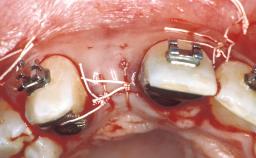

A healthy 32-year-old male patient presented at the clinic for a consultation on treatment options to replace his failing central incisors and retained deciduous canine. This case review addresses the treatment of the central incisors. At full smile, the patient exhibited a medium lip line with tapered clinical crowns and a thin-gingiva biotype. A retracted view of the central incisors showed a discrepancy in the gingival margin positions of teeth 11 and 21. A radiographic examination revealed that teeth 11 and 21 were subject to external and internal resorption and that an impacted canine was present. A clinical and radiographic examination showed good circumferential bone support of the anterior teeth. A detailed examination was performed to determine the esthetic risk profile for this patient.